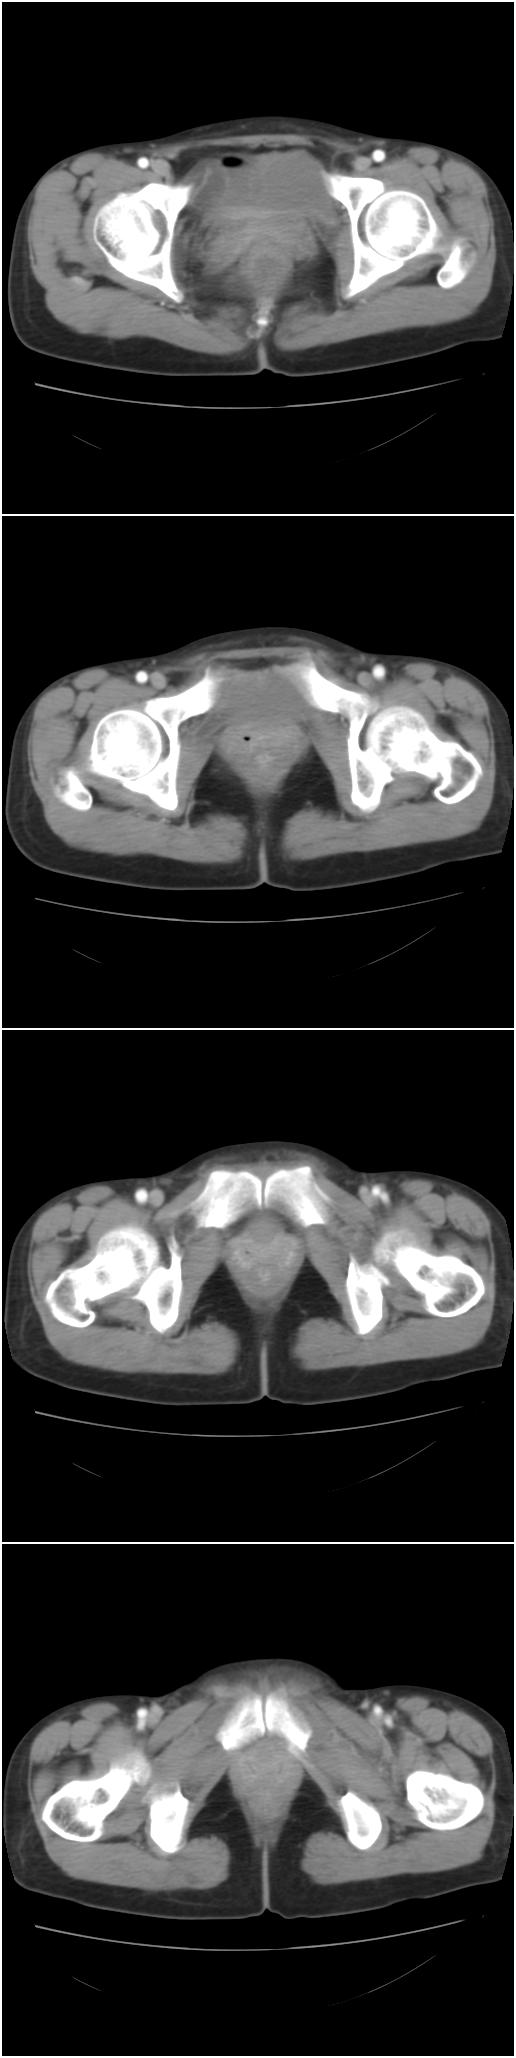

以下是今天的增强片,大家可以看看:

右髂骨见一类圆形略高密度区,似见分层,骨质破坏不明显

考虑良性病变,以动脉瘤样骨囊肿可能性大

右侧髂骨后缘囊状膨胀性骨质改变,无明显骨间隔,周围无明显硬化及骨膜反应,周围软组织无异常,相邻骨组织密度增高,考虑:动脉瘤样骨囊肿可能,要注意与骨巨细胞瘤及转移瘤鉴别。

右侧髂骨膨胀性骨质破坏区 囊内密度尚均匀 骨巨细胞瘤可能性大 动脉瘤样骨囊肿不除外 建议mr观察囊内成分明确诊断 左侧附件区包裹性积液

该病人今天做了增强,右侧髂骨病灶明显强化。

右侧髂后上棘局限性囊状骨质破坏,大部分界清,似见轻度硬化边,内无分格及钙化,病灶上部局部显示模糊。考虑;骨巨细胞瘤可能大,不除外abc。另可见子宫肌瘤术后子宫缺如。

临床和影像学表现:女性患者46岁,有子宫肌瘤手术病史。影像所见可见残余宫颈部分,左右附件未见新生物;右髂骨翼后端囊状膨胀性骨破坏,囊性部分感觉有强化(楼主标上增强前后的ct值就很好了),未见明确的液—液平面,周边硬化不明显或轻度硬化。

分析:患者年龄46岁,没有明确外伤病史,病变呈膨胀性骨破坏,囊性部分未见明确的液—液平面,周边硬化不明显。综合分析该病例比较符合骨巨细胞瘤,不太符合动脉瘤样骨囊肿。

诊断:1、首先考虑骨巨细胞瘤;2子宫肌瘤术后改变